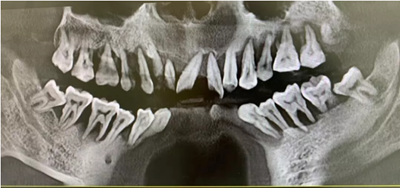

這是一個三十多歲的小伙子牙周炎的最終歸宿——全口牙松動,拔除。在口腔大夫那里,這些病例已經(jīng)司空見慣了,一句話形容:看起來,他們一顆牙也不缺,其實,已經(jīng)一顆牙也不在了!

圖為大量齦下結石刺激導致牙齦廣泛充血腫脹,牙齒松動,局部已形成牙齦瘤,治療上比單純牙周炎復雜。